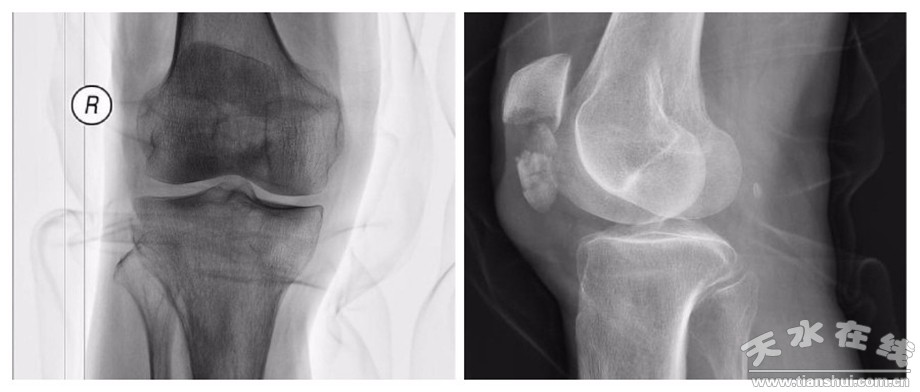

80岁男性患者,意外摔伤导致右膝部疼痛、活动受限,经急诊拍片检查提示“右侧髌骨下极粉碎性骨折”。

患者收住市一院运动医学科后,进一步完善三维CT,检查提示“髌骨下极存在多个大小不一的碎骨块,骨折线累及髌骨下1/3关节面”。